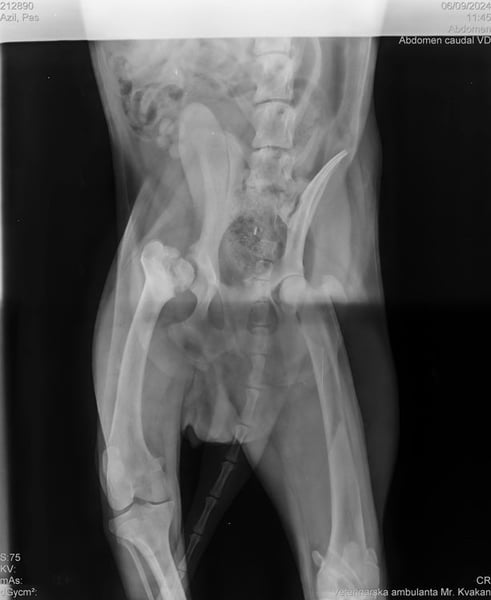

Bemerkungen: Ein Hinterbein ist etwas kürzer

Wir durften ihn deshalb ohne Probleme mit ins Tierheim nehmen, da Yondu Probleme mit der Hüfte und ein etwas kürzeres Beinchen hat. Youdu hat bei einen Besuch beim Tierarzt entsprechende Röntgenbilder von Hüfte und Hinterbeinchen, die den Interessierten in der Bildergalerie zur Verfügung gestellt werden.